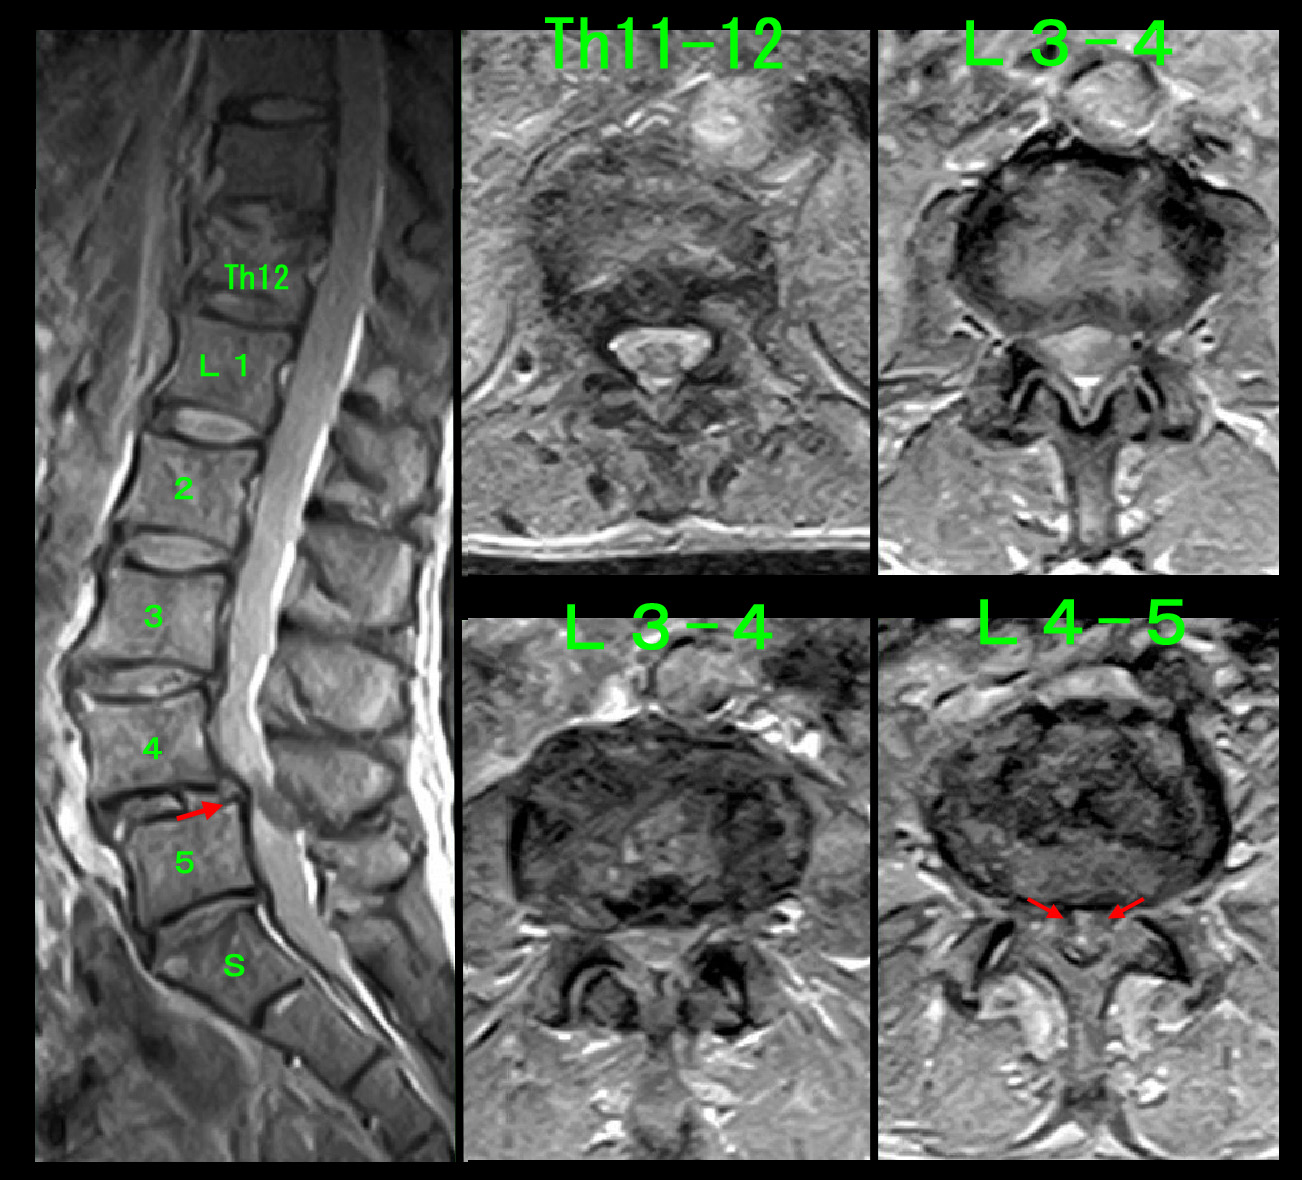

82才男 MR1.jpg

腰椎MRI検査ではL45で重度の脊髄の圧迫(赤矢印)が確認されます。第12胸椎圧迫骨折に起因するオレンジ丸領域の腰痛が軽減して、元々あった腰椎の老化による脊髄圧迫による腰痛と右足指の坐骨神経痛が症状を出したのだと判断します。そこでL45高位で足指の痛みある左側の神経根ブロックを施行しました。